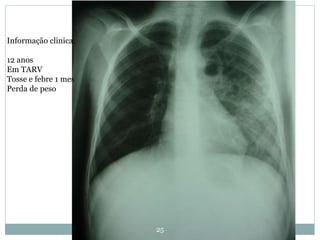

Informação clinica:

12 anos

Em TARV

Tosse e febre 1 mes

Perda de peso

25 Informação clinica: 12 anos EmTARV Tosse e febre 1 mes Perda de peso